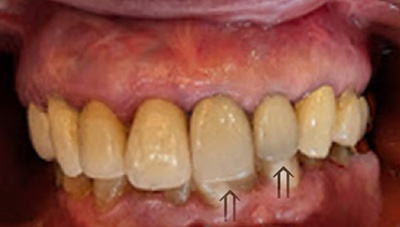

年前の症例

掲載写真撮影:2025年(88歳/女性)

セラミック(陶歯前装冠):1970年(年前)当時33歳

矢印(⇑)の2歯は、当時主流のセラミック(陶歯前装冠)です。

抜歯することもなく、咀嚼に問題なく、88歳の現在、顔面に縦ジワは見られません。